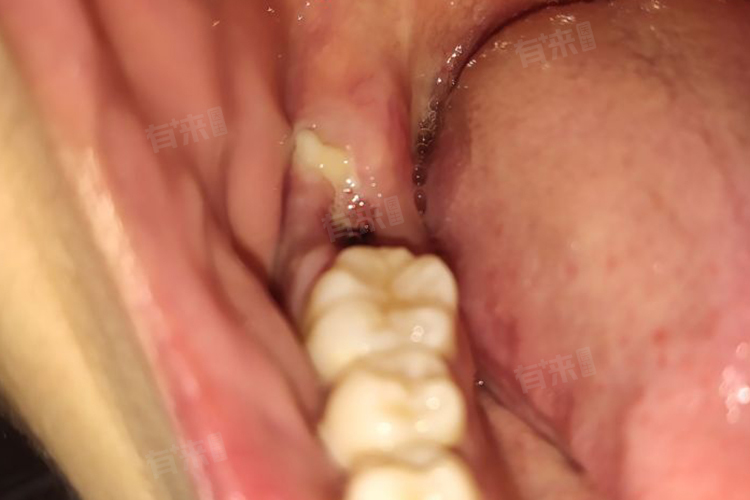

2、伪膜形成:拔牙后局部会有出血点,随后形成血凝块,机化后在拔牙缝线处形成白色的伪膜,该伪膜对牙槽窝有一定的保护作用,属于正常现象。通常不需要特殊处理,但应注意保持口腔卫生,避免感染。

4、局部感染:如果拔牙后口腔卫生不清洁,容易导致牙槽窝感染,形成脓性分泌物或白色坏死组织,建议在医生的指导下进行局部清创,并使用抗生素进行对症治疗。

5、局部坏死:可能与缝线过紧有关,导致牙龈局部组织发生坏死,进而引发肉发白。如果伴有疼痛或不适,建议及时到医院就诊,医生会根据情况进行相应处理。